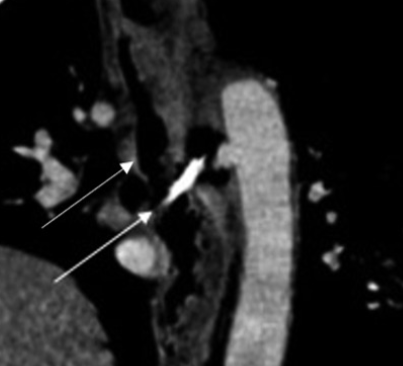

La perforación esofágica secundaria a cuerpos extraños es una patología infrecuente. Puede ser asintomática o asociarse a complicaciones como mediastinitis, perforación aórtica o incluso pericárdica. La fístula aortoesofágica por perforación esofágica se asocia a alta mortalidad siendo fundamental su manejo precoz.